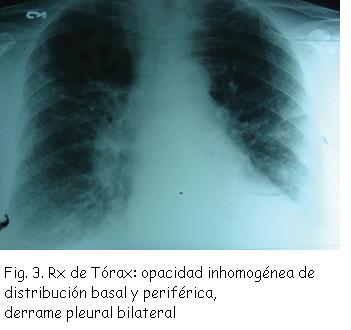

Radiografía de Tórax: opacidad inhomogénea de distribución basal y periférica, derrame pleural bilateral (Figura 3).